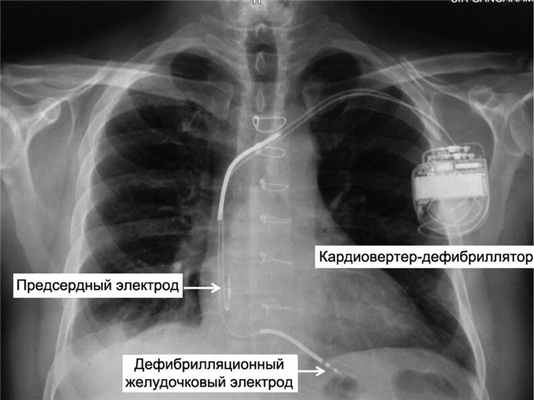

Имплантируемые кардиовертеры-дефибрилляторы (ИКД) в профилактике ВСС; первичная и вторичная профилактика ВСС. Проблема профилактики ВСС — краеугольный камень современной аритмологии [15]. ИКД являются одним из основных методов в концепции профилактики внезапной смерти. Основное предназначение ИКД состоит в нанесении антитахикардической стимуляции (АТС) и/или высокоэнергетического шокового разряда, направленного на купирование опасных для жизни желудочковых аритмий, которые являются ведущими в механизме ВСС [16] (рис. 1). Рис. 1. Рентгенограмма грудной клетки в прямой проекции пациента с двухкамерным ИКД. Электроды установлены в правом предсердии и правом желудочке.

Электроды

Имплантируемый дефибриллятор через вены соединяется с сердцем посредством специальных электродов. Электроды крепятся в полости правого предсердия и в полости правого желудочка. В зависисмости от вида ИКД (однокамерный, двухкамерный, трехкамерный) каждый электрод имеет свои конструктивные особенности и предназначен для стимуляции одной из камер сердца.